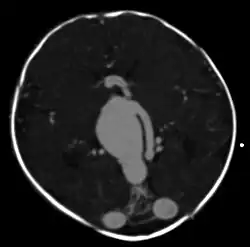

| Axial image from computerized tomography angiogram showing arteriovenous communication in vein of Galen malformation | |